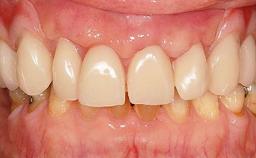

A 93-year-old female patient presented in September 2010 with an enlarged swelling on the lingual side of her lower incisors. At the time, she was essentially healthy, except for reduced vision due to bilateral age-related macular degeneration. She had been a heavy smoker (about 30 cigarettes a day) for the past 20 years after becoming a widow. The patient lived at home by herself, with full-time domestic support. An extraoral examination revealed nothing adverse. Intraoral plaque control was anything but ideal, and a soft-tissue tumescence was visible around the lingual aspect of 41–42. Because the nature of the lesion was not clear, a biopsy was carried out that revealed the inflammatory nature of the lesion. The panoramic radiograph showed six irregularly distributed mandibular implants supporting a full-arch prosthesis, with various degrees of interproximal peri-implant resorption. The periapical radiograph revealed interproximal bone resorption mesially and distally to implant 41.